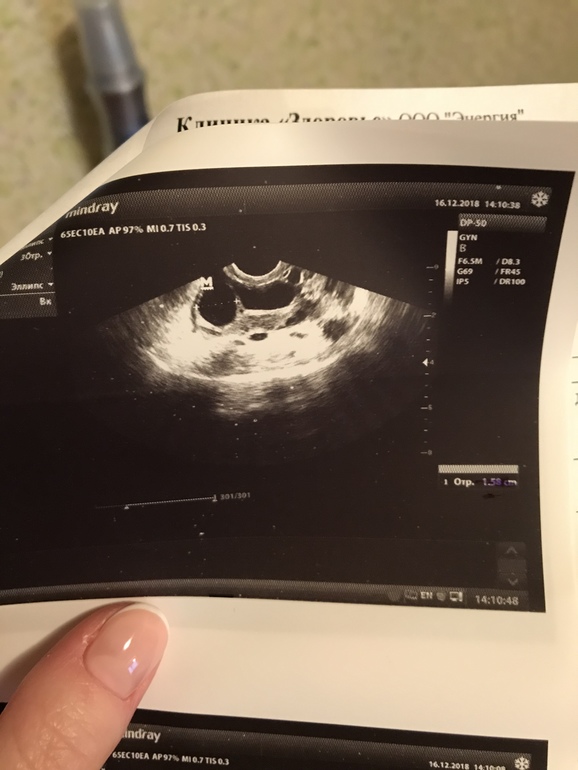

Два фолликула, один неправильной формы

У кого была похожая картина на УЗИ, чем закончилась? Я думала что один замедлится в росте, как обычно бывает, но они оба растут одинаково. При том надежды были на бОльший, он сейчас 19 мм, но Г сказала что он неправильной формы и не очень похож на полноценный фолликул. А вот второй, который думали что регрессирует наоборот стал красивый, но он всего 15 мм((( а овуля должна быть завтра по циклу. Как бы вообще без полноценной овуляции не остаться 😔